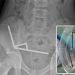

13-year-old boy has emergency surgical procedure after swallowing 100 magnets

A 13-year-old New Zealand boy had a part of his intestines eliminated after swallowing greater than 100 high-powered magnets believed to have …